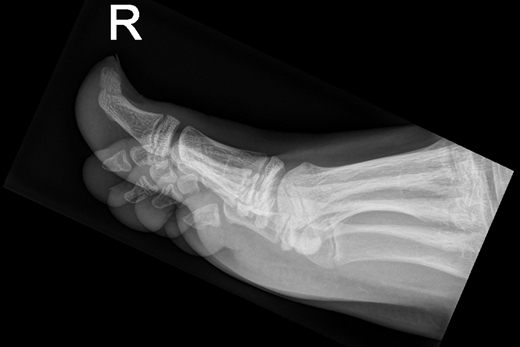

Twee patiënten bezoeken kort achter elkaar de huisarts, omdat ze een zwelling onder een nagel hebben. Na onderzoek blijkt het te gaan om een subunguale exostose, een zwelling onder de nagels van tenen of vingers. Vanwege de zeldzaamheid van deze aandoening duurt het enige tijd voor de huisarts de diagnose stelt. Wat moet u doen bij een patiënt met een zwelling onder de nagel?